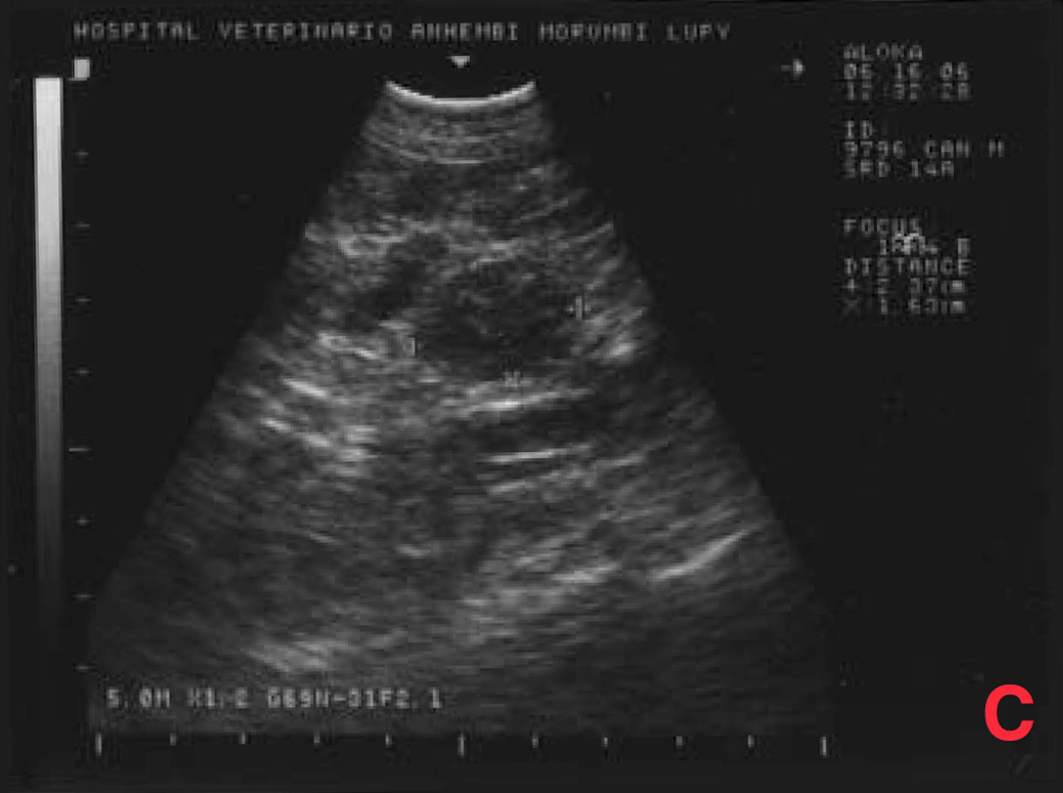

Não houve alterações na avaliação hematológica, na bioquímica (creatinina, ureia) e na radiografia torácica, porém o exame ultrassonográfico mostrou aumento de próstata (4,3 x 3,8 x 2,8cm), com áreas císticas difusas pelo parênquima (imagens sugestivas de hiperplasia prostática benigna/prostatite); somente um testículo em bolsa escrotal; grande aumento de volume em região inguinal esquerda (formação heterogênea em ecotextura e ecogenicidade) e aumento de cadeia de linfonodos sublombares e ilíacos (medindo até 2,4 x 1,6cm, com ecogenicidade e ecotextura heterogêneas) (Figura 3).

Após vinte dias, o estado do animal era bom. Realizou-se então um exame ultrassonográfico de controle, através do qual se observou que o volume da próstata continuava crescendo e que os linfonodos sublombares e ilíacos tinham aumentado, passando a medir 5 x 3,8 x 3,2cm, com ecogenicidade e ecotextura heterogêneas, devendo-se considerar a possibilidade de processo metastático.

O exame ultrassonográfico demonstrou aumento de próstata mais acentuado (6 x 5 x 5,6 cm), com áreas císticas/cavitárias difusas pelo parênquima (sugestivas de hiperplasia prostática benigna/prostatite/neoplasia) e aumento de cadeia de linfonodos sublombares e ilíacos (5 x 4,6 x 4 cm), com ecogenicidade e ecotextura heterogêneas, sugestivo de processo metastático (Figura 9).